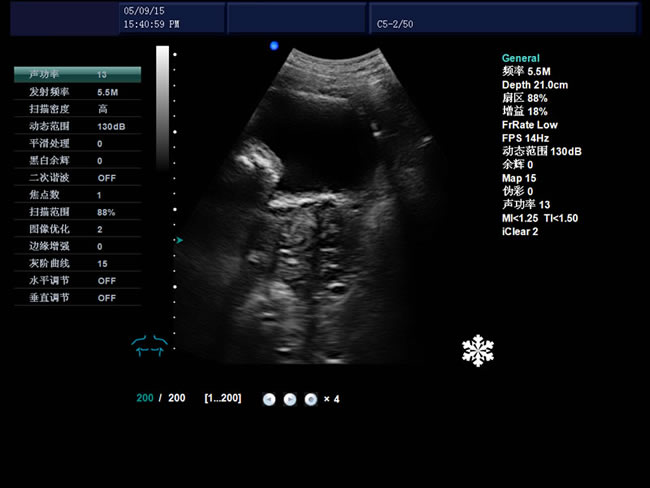

S8 彩色多普勒獸用超聲診斷儀

• S8彩色多普勒獸用超聲診斷儀是徐州市大為電子設備有限公司推出的一款全新的彩色超聲診斷儀器。

1、檢查母豬的空懷,降低無效飼養的功效早已深入人心

2、用B超監測可及早準確掌握妊娠母豬頭數,較高的早期妊娠診斷準確率較好的保證了均衡生產

3、探查時間短、無應激、準確率高,而且產生巨大的生產應用價值